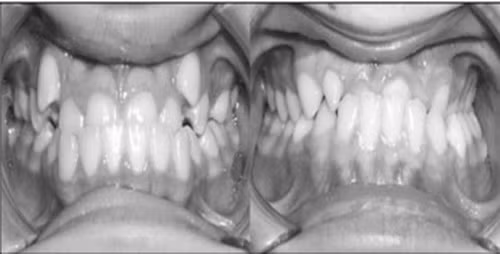

Khớp cắn ngược (móm)

Khớp cắn hở: Khi cắn 2 hàm răng lại, răng hàm phía sau chạm nhau nhưng răng cửa vẫn hở. Răng trên và các răng dưới không chạm nhau.

Cần đưa trẻ đến khám bác sĩ chuyên khoa răng hàm mặt khi trẻ có bất thường trong sự phát triển của răng, quá trình mọc răng và thay răng sữa, quá trình phát triển và mọc răng vĩnh viễn. Có thể nêu một số ví dụ như: răng xoay hay các răng mọc chen chúc, răng mọc sai vị trí, răng xô lệch, không ngay ngắn trên cung hàm; thiếu răng bẩm sinh, răng dị dạng và răng dư, răng sữa mất sớm, răng chậm thay, răng di chuyển do chấn thương; trẻ có những thói quen xấu về răng miệng có thể gây sai lệch khớp cắn và những lệch lạc về răng và hàm mặt ví dụ như: mút tay, mút môi, tật đẩy lưỡi, thở miệng; có những biểu hiện sai khớp cắn như cắn chìa, cắn sâu, cắn chéo, cắn hở, hô, móm; có sự phát triển lệch lạc giữa xương hàm trên và hàm dưới như cung răng và xương hàm hẹp; răng nhô ra trước hoặc răng thụt vào trong, xương hàm nhô ra trước hoặc xương hàm lùi ra sau...